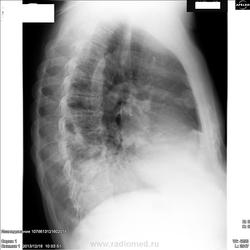

боковой снимок к первому или второму в прямой проекции относится?

Проследите изменения и ответьте сами на свой вопрос.

можно предварительно рассматривать как двухсторонний инфильтративный туберкулез легких в фазе распада. Жаль нет левой боковой рентгенограммы.

Ну,простите,коллеги,без бока,да не резал,непохоже на меня,да уж последний день перед отпуском.Смежники пусть хоть немножко поработают.